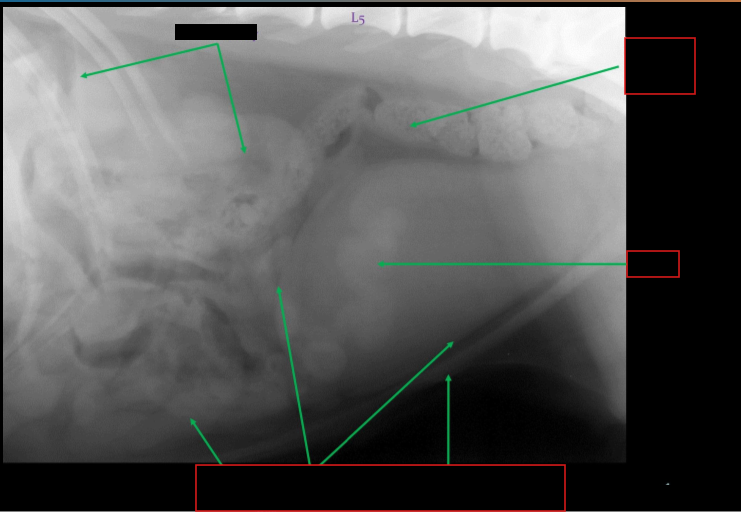

Label this radiograph of a bitch